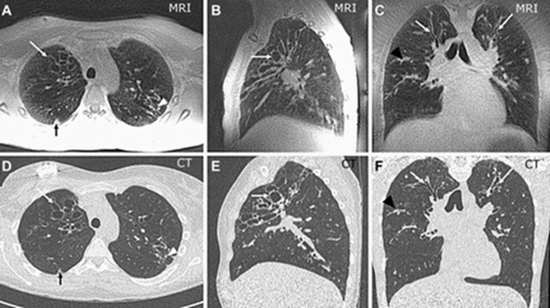

بررسی همبستگی یافته های MRI و CT اسکن در بیماران مبتلا به سیستیک فیبروزیس در مرکز طبی

بررسی همبستگی یافته های MRI و CT اسکن